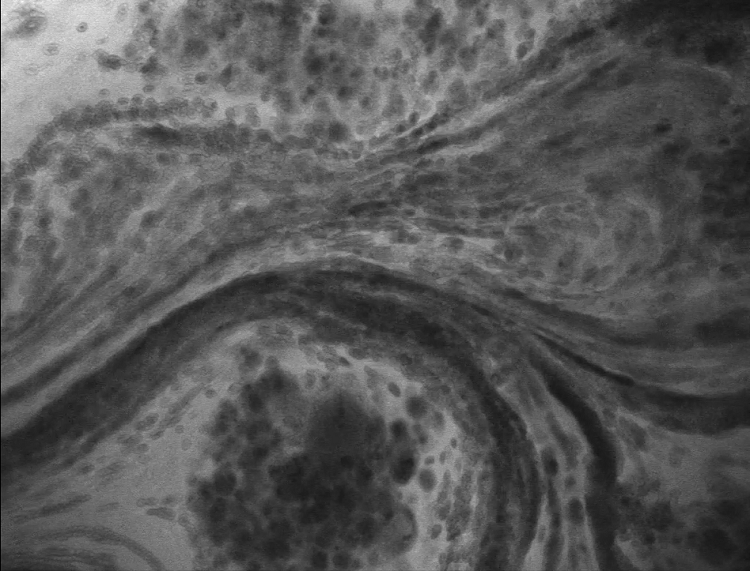

8、腦膠質(zhì)母細(xì)胞瘤OptiScan成像

注:活大鼠腦中被滲漏血管包圍的腫瘤病灶。該腫瘤為惡性膠質(zhì)瘤,浸潤(rùn)性強(qiáng),可引起出血。這里使用的造影劑是靜脈注射熒光素。在本實(shí)驗(yàn)中,注射了IV熒光素。它分布在整個(gè)動(dòng)物周?chē)?,可以看到血液通過(guò)血管流動(dòng)。為此,頭骨需要被打開(kāi)或變薄。大型動(dòng)物的硬腦膜也需要手術(shù)打開(kāi)。Scale bar=100μm。